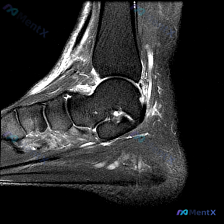

踝关节MRI看到多部位高信号,别只想到足底筋膜炎!

今天分享一例踝关节矢状位T2序列MRI的读片病例,整理了完整分析思路,和大家一起讨论。

检查部位:踝关节MRI-T2序列-矢状位

可见解剖结构:胫骨远端、距骨、跟骨及部分跗骨

核心影像异常表现

- 骨组织:距下关节跗骨窦区可见高信号影,距下关节面上方伴异常液体信号;跟骨内部靠近跖筋膜附着点及跟骨体部可见散在点片状高信号,提示局部炎症或应力反应。

- 韧带肌腱:跖筋膜在跟骨足底附着处起始端形态增厚,伴明显高信号,提示软组织炎症或变性;跟腱止点处及跟腱前滑囊区域信号轻度增高,提示轻度炎症;

- 软组织:足底皮下脂肪及筋膜层可见弥漫性高信号,提示软组织水肿或炎症。

首先看到的最直接异常就是多个区域的T2高信号,也就是软组织液体/水肿,病变同时累及了足底筋膜附着处软组织、跟骨局部骨组织、跗骨窦区域,属于多点位的异常改变。

这个病例最值得注意的点是:病变不是局限在单一结构,而是同时累及了足底筋膜附着点、跗骨窦、跟骨、跟腱止点四个部位,这种多部位炎性改变的模式需要我们拓宽鉴别思路。